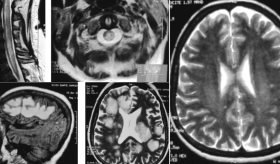

En cuanto al diagnóstico, si se sospecha un colangiocarcinoma, el médico puede realizar diversas pruebas como análisis de función hepática y del marcador tumoral CA 19-9, que pueden sugerir la presencia de cáncer.

También se emplean estudios por imágenes como ecografía, tomografía computarizada y resonancia magnética. En algunos casos se utiliza la colangiopancreatografía retrógrada endoscópica para observar directamente los conductos y tomar muestras o biopsias.